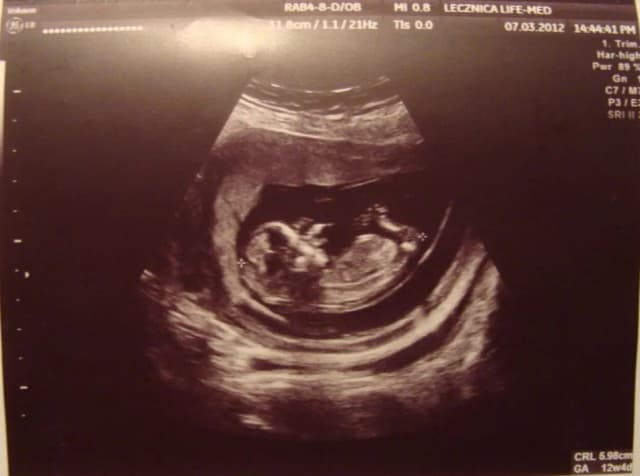

Tag co się dzieje z dzieckiem w 13 tygodniu ciąży